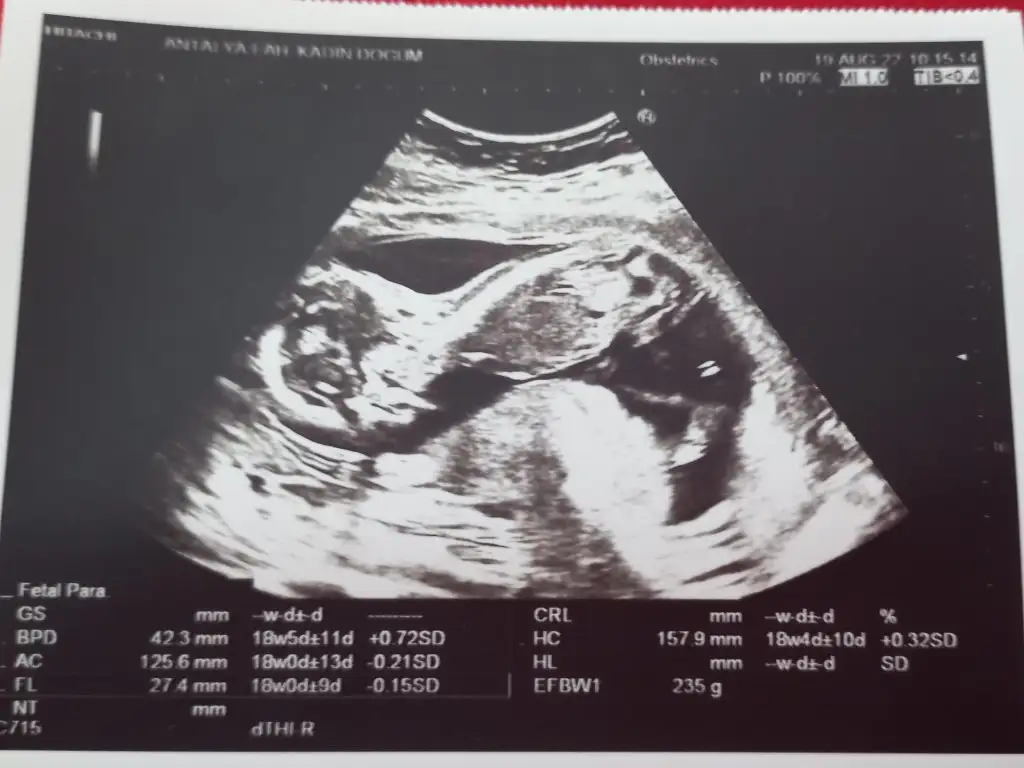

Maşallahhh imanlı bir çocukBende dün gittim 235 gram olduk ama kız gene namaz kılıyor gibi pozisyonda3 ağustosta aynı doktora gittim o zaman da çok güldük ve dün aynı oldu